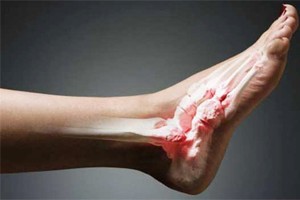

- Открытые. Присутствуют раны, которые кровоточат, и костные осколки в них. Наблюдается формирование отечных процессов и деформация ноги.

- Открытого типа. При нем пациент может самостоятельно увидеть оголенную кость. Такие переломы связаны с разрывом тканей.